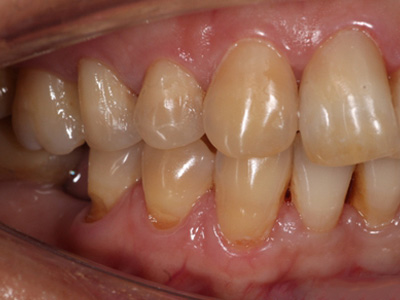

楔状缺损是一种非龋性牙颈部慢性损伤,是指发生在牙齿唇、颊面颈部的慢性硬组织缺损。典型缺损由两个夹面组成,口大底小,呈楔形。楔状缺损多发生于中老年人,主要原因是刷牙不当,防治措施是调整咬合关系,改善刷牙方法,配合相应的治疗。

楔状缺损与年龄相关,即年龄越大,缺损越重,患者多有横刷牙习惯,患牙为多颗甚至全口,常以口角附近的牙齿(尖牙、前磨牙)为重。典型表现为牙颈部缺损,呈楔形,由两个夹面组成,口大底小,缺损处质地坚硬,表面光滑,边缘整齐,无染色,轻微泛黄常为牙齿本色,严重时可导致牙髓腔暴露甚至牙齿横向折断,根据缺损深浅不同,可伴有牙齿敏感甚至疼痛。

如果楔状缺损不深、症状不明显,可以不处理,有过敏症状可进行脱敏治疗。楔状缺损较深者可行充填修复。缺损达到牙髓腔,导致牙髓感染、根尖周病或牙齿横折者,可进行根管治疗、拔除患牙,再进行修复。平时要采取正确的刷牙手法,例如巴氏刷牙法,避免咬硬物。必要时通过正畸、修复等方法调整咬合关系。